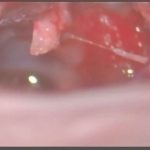

術中写真

摘出 後